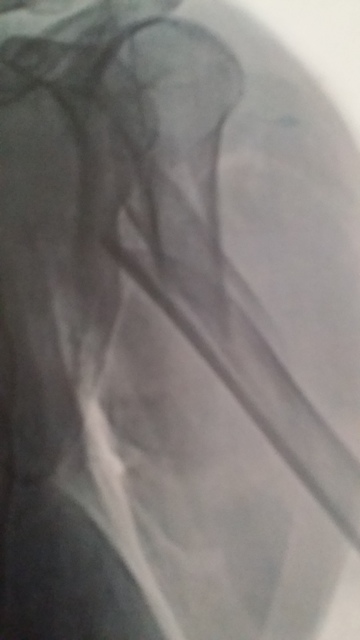

I had this to deal with

Learned to do a lot with one hand

I did the same thing to my right arm a couple of years ago. Of course I'm right-handed!